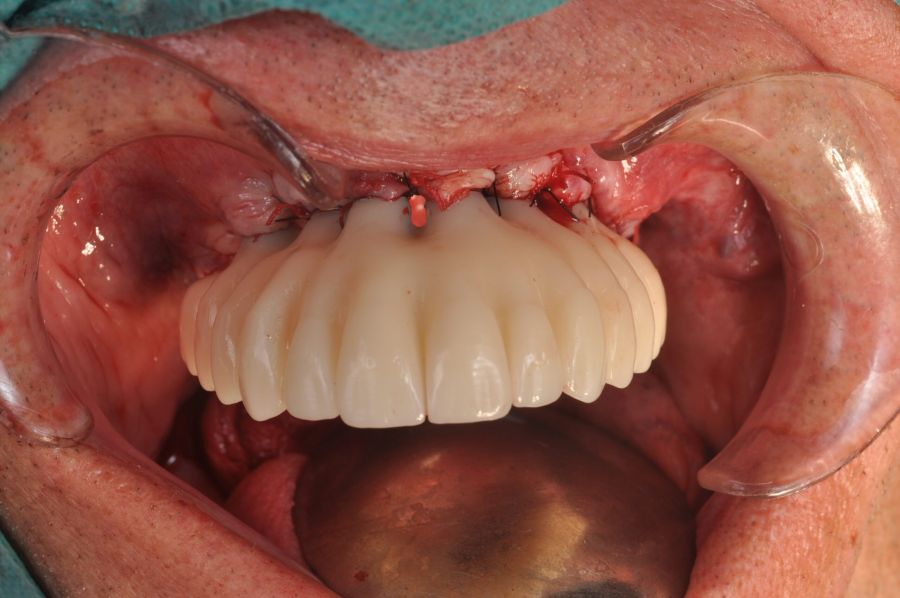

The surgical procedure was performed under general anaesthesia and nasotracheal intubation. A supracrestal incision and detachment of a maxillary flap of total thickness was made (Figures 9 and 10). The boundaries of the dissection were both infraorbital ridges, both laterally malar bodies and the anterior half of the hard palate caudally. In addition, a customized cutting guide was used so that the SI was completely in direct contact with the bone (Figure 11) and the mesh was fixed with the different 1.5 mm osteosynthesis screws in the nasal and zygomatic buttresses (KLS Martin, Freiburg, Germany) (Figure 12). The closure was performed with nonresorbable suture. Finally, the PMMA provisional rehabilitation was screwed for the immediate load, with a torque of 20 N on the implants (Figures 13-15).